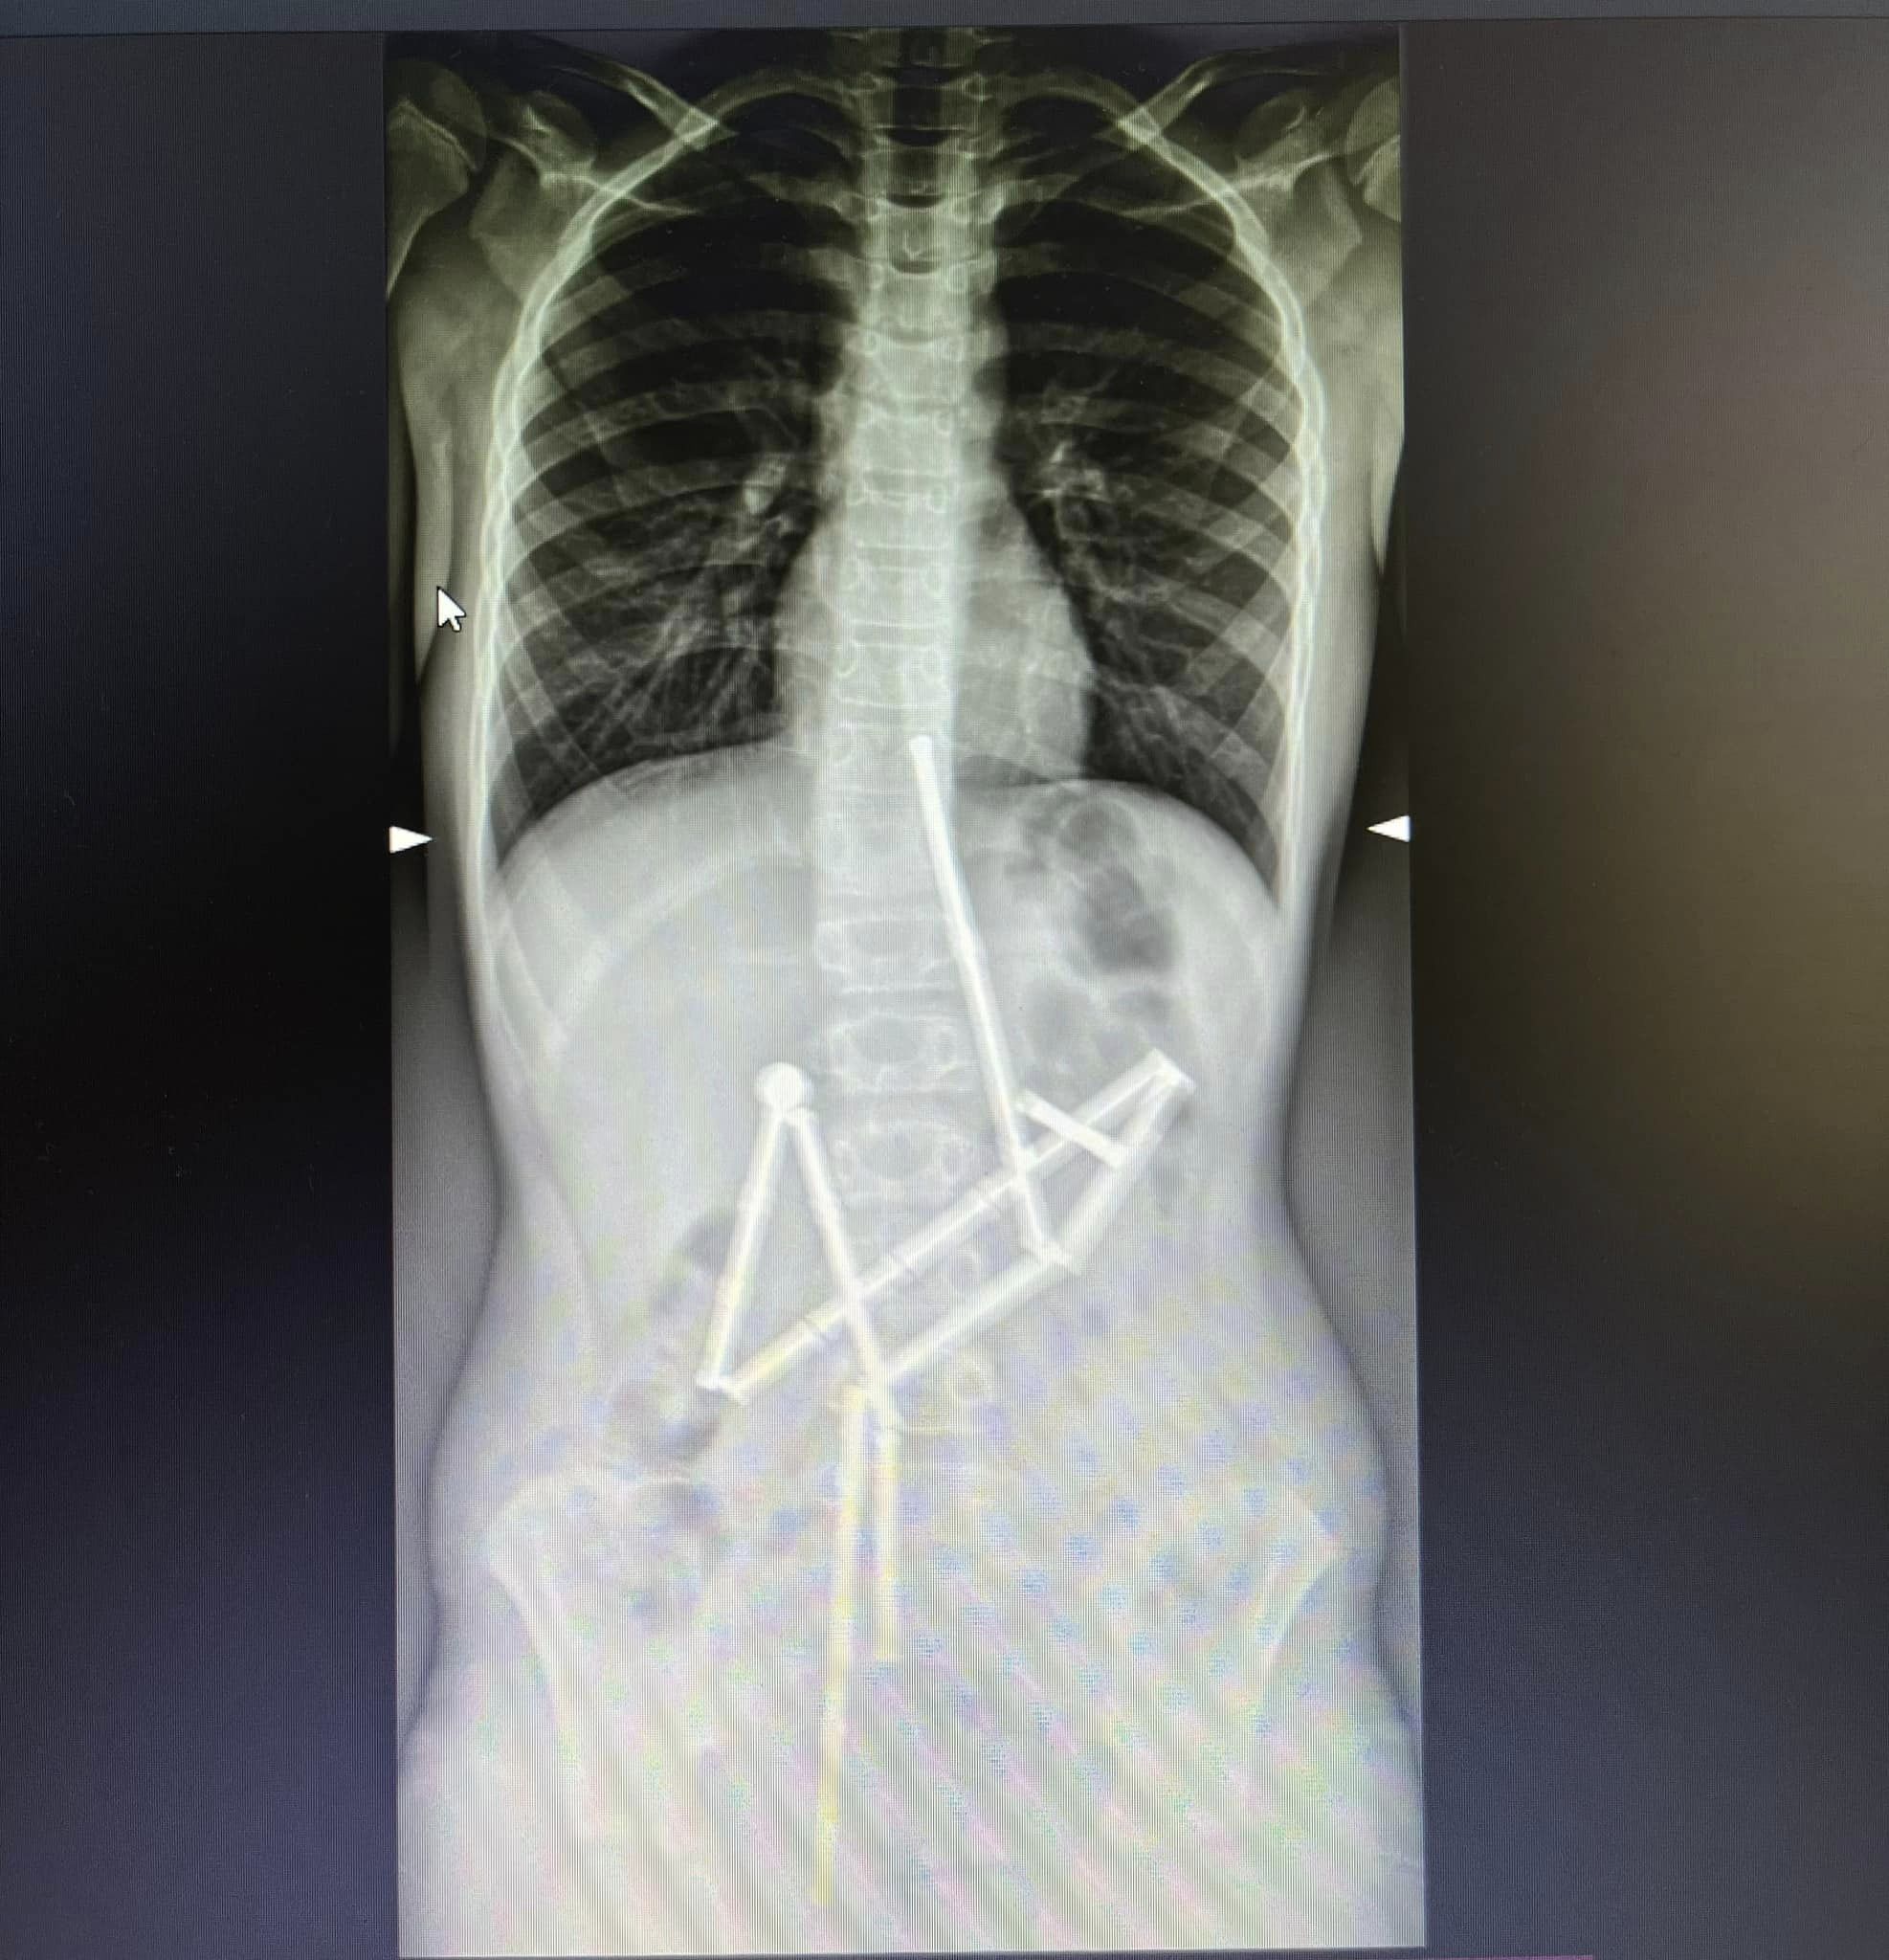

"<...> Уже на первом рентген-снимке специалисты увидели наличие в пищеварительном канале целой группы инородных тел, в которых удалось узнать магнитный конструктор. 20 магнитов находились в разных частях желудочно-кишечного тракта, и были соединены между собой. Консилиумом врачей было принято решение о проведении неотложного оперативного вмешательства", - сообщают в клинике.

"Отличие магнитов от других предметов, которые могут проглотить дети, заключается в их притягивании друг к другу и в ущемлении тканей. Как следствие, возникают зоны некроза (омертвения), перфорации полых органов, желудочно-кишечные непроходимости", - пояснили медики.